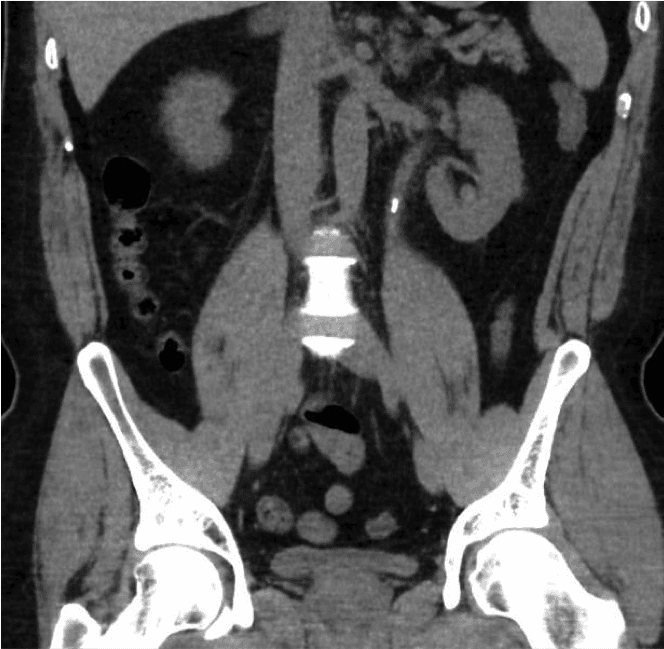

சிறுநீரக கல் நோய் என்பது நவீன யுகத்தின் மிகவும் பொதுவான நோய்களில் ஒன்றாகும். மேற்கத்திய நாடுகளில் ஆண்களில் 8% முதல் 19% வரையிலும், பெண்களில் 3% முதல் 5% வரையிலும் பரவல் புவியியல் இடங்களுக்கு இடையில் பெரிதும் வேறுபடுகிறது [1,2]. 2000 முதல் 2010 வரை இங்கிலாந்தில் சிறுநீரக கற்களால் ஏற்படும் மருத்துவமனை எபிசோட்களின் எண்ணிக்கை 63% அதிகரித்து 83 050 ஆக அதிகரித்துள்ளது [3]. கல் நோயின் அதிகரித்து வரும் பரவல் நமது சுகாதார அமைப்பில் ஒரு பெரிய பொருளாதார மற்றும் மருத்துவ சுமையை ஏற்படுத்துகிறது.வேறு காரணங்களுக்காக செய்யப்படும் ஸ்கேனில் சிறுநீரக கற்கள் தற்செயலாக தோன்றலாம் அல்லது வலி, சிறுநீர் தொற்று அல்லது ஹெமாட்டூரியா (சிறுநீரில் இரத்தம்) போன்ற அறிகுறிகளுடன் இருக்கலாம்.

சிறுநீரக கற்களின் அறிகுறிகள், நோயறிதல் எவ்வாறு செய்யப்படுகிறது மற்றும் சிகிச்சை விருப்பங்கள் பற்றிய தகவல்களை பின்வரும் இணைப்புகளைக் கிளிக் செய்வதன் மூலம் காணலாம்.கற்கள் உருவாவதைத் தடுப்பதற்கான ஆலோசனைகளுடன் கூடிய உணவுமுறைத் தகவல் துண்டுப்பிரசுரமும் உள்ளது.